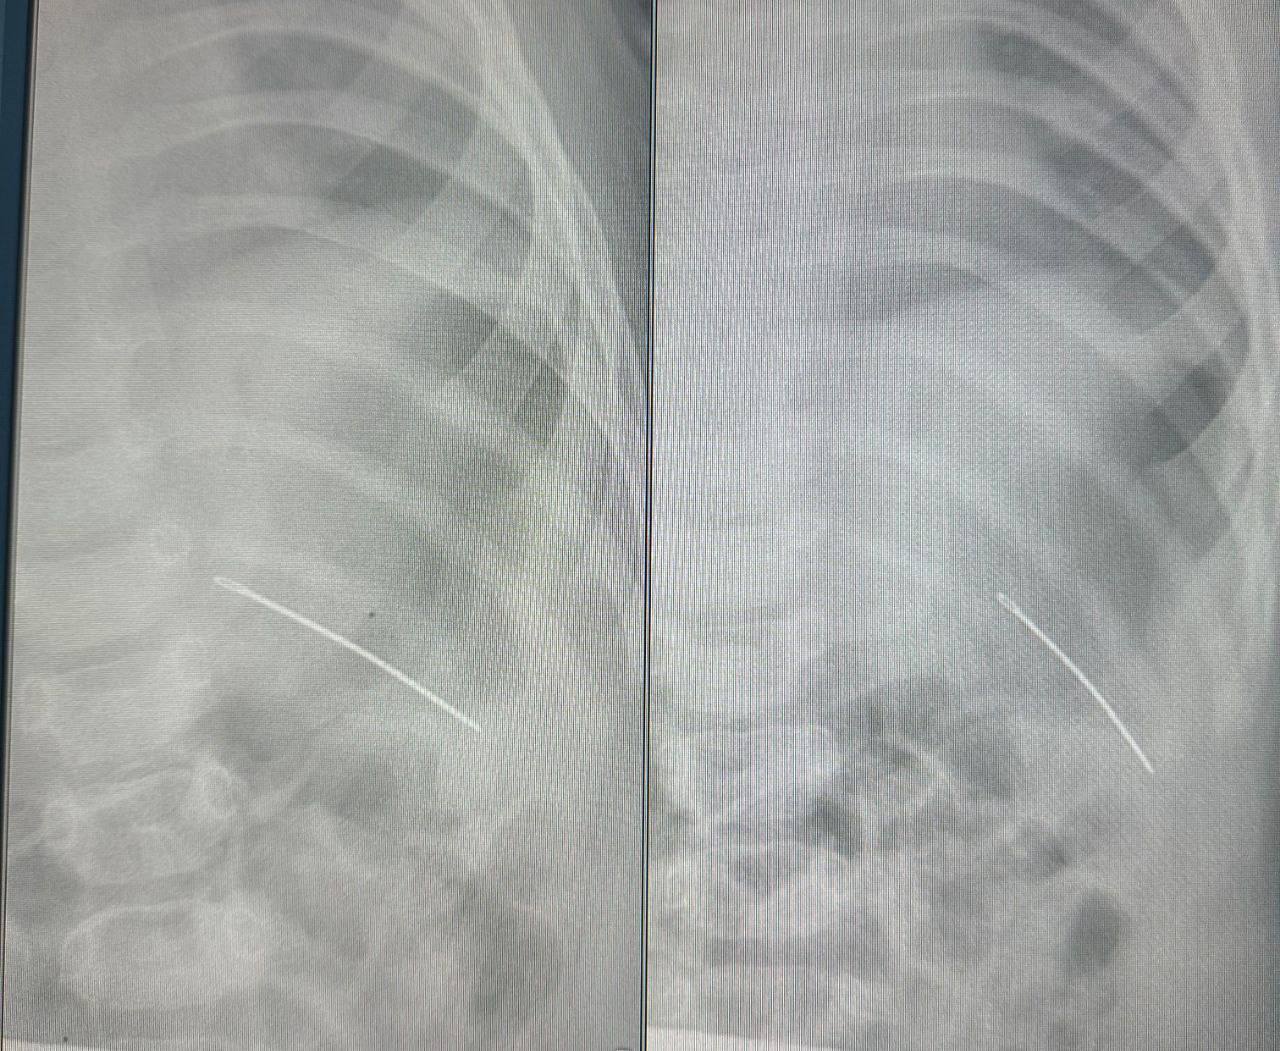

Фото: Министерство здравоохранения Самарской области

Врачи провели диагностические исследования — рентген ключицы и тазобедренного сустава. По результатам исследования определили, что в грудной клетке ребенка находилась швейная игла. Случай оказался непростым: возможно, в результате падения игла зашла чрез кожу снаружи, проткнув насквозь ребро. В результате чего у девочки были затрудненные движения левыми рукой и ногой. Медицинские работники оперативно приняли решение об операции и безопасно удалили инородное тело, сообщает пресс-служба областного минздрава.

Детский хирург областной клинической больницы Дмитрий Быков отметил, что если бы игла оказалась на 2 сантиметра выше, она могла бы попасть в сердце, что создало бы непосредственную угрозу для жизни.